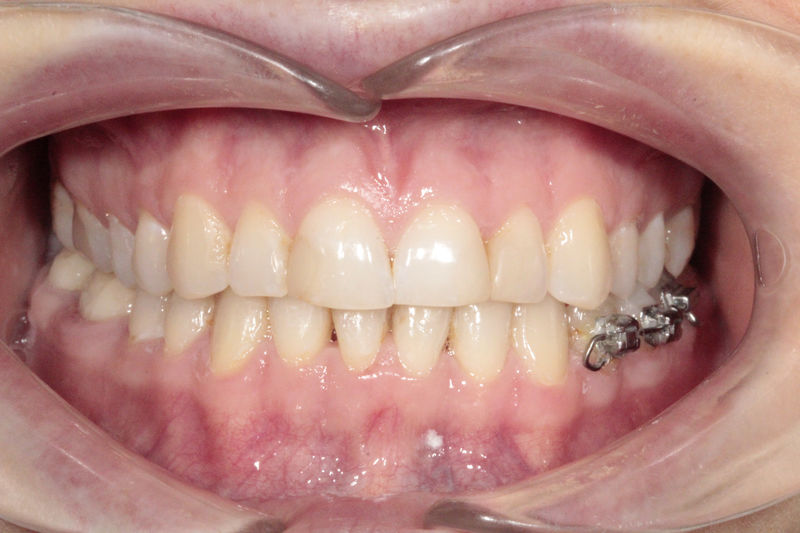

Implantes, ortodoncia y coronas.

Ortodoncia y coronas.